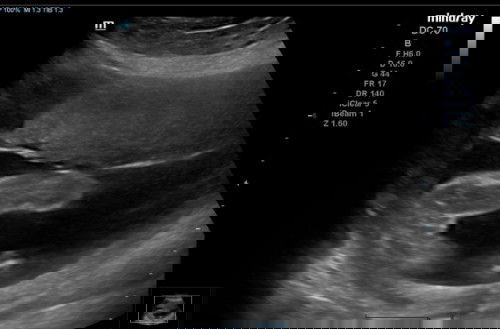

Ibu2 confirm ke baby girl ni?